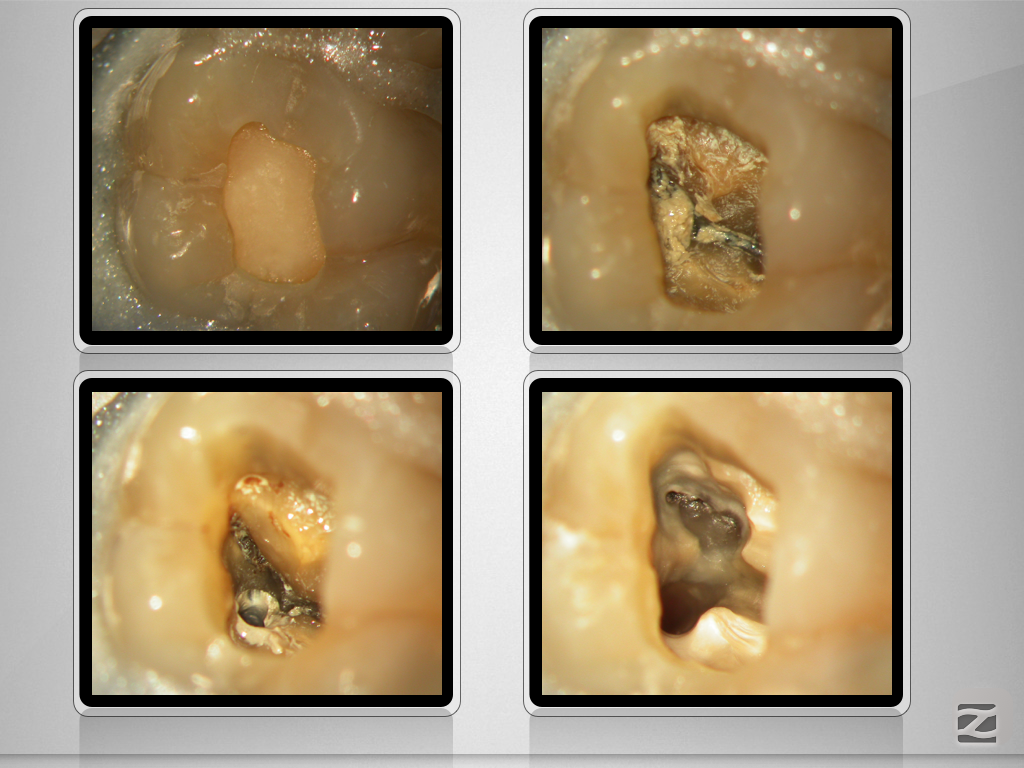

X-Bein- mit Überlegung zum Erfolg